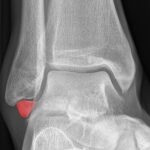

[doctormodu]1 os subfibularae

14 비골하 골편 Os subfibularae

닥터모두

3 발목, 발4하지Lower Extremities

2025.10.25

42

#6